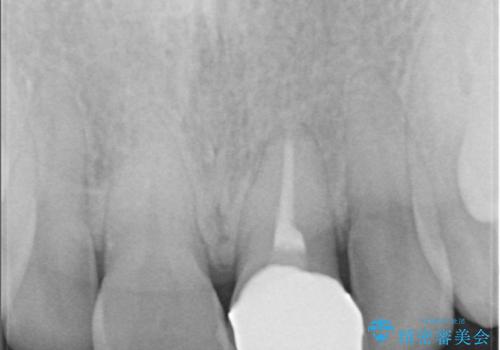

過去に神経の治療をした歯に変色がみられました。ラバーダム防湿の重要性を説明し、予防的に再根管治療から行い、被せ物をすることとなりました。

なるべく隣の歯と調和するようにしました。大変ご満足いただけました。